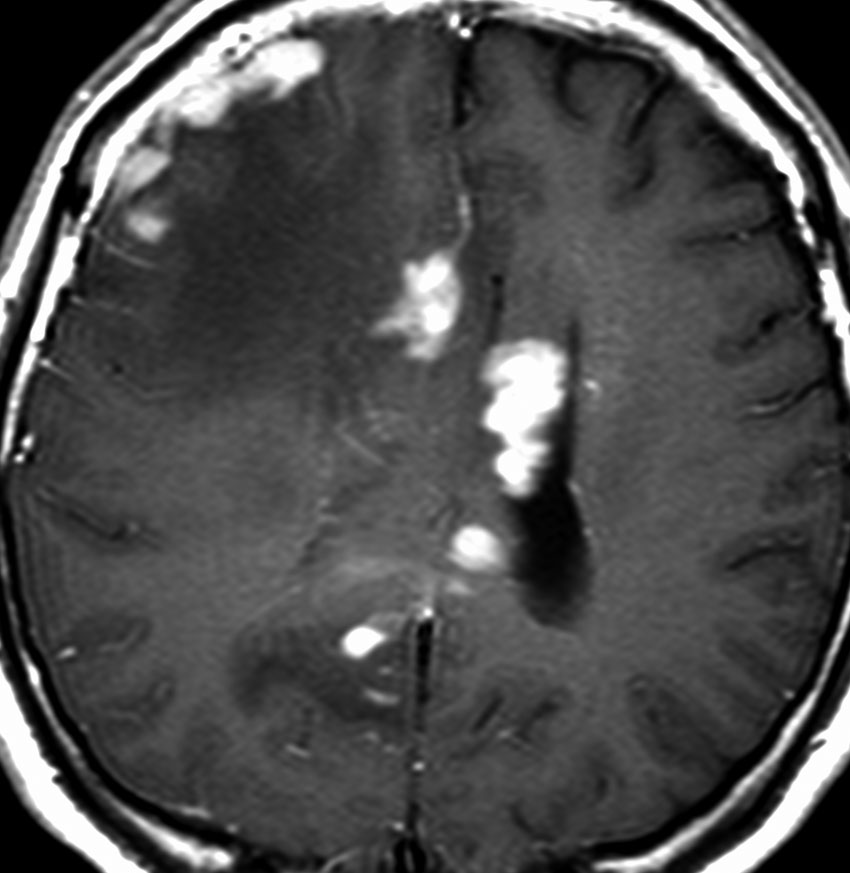

MRI検査で,はっきりわかります。MRI造影剤を入れると均一または斑らに増強(真っ白になる)されて(左側),周囲には脳の腫れ(脳浮腫)がみられます(右側)。できやすい場所は側脳室の周囲・大脳脳基底核・小脳・脳幹部など脳の深いところ(深部白質)です。脳の中に2個以上のリンパ腫が同時にできる多発例というのもしばしばあります

若い患者さんのリンパ腫です。左が診断時MRIで,黄色の矢印でみれる3ヶ所に同時にリンパ腫が発生しています。定位生検術後にすぐにMTX化学療法を3コースしたら,真ん中の画像になりました。ほとんど消失しているのですが,矢印の先にぼーっと少し残っているのでCR(消失)とはいいません。化学療法を終えた後に全脳照射30グレイをしたら右の画像になり治りました。これは順調な治療経過の例です。